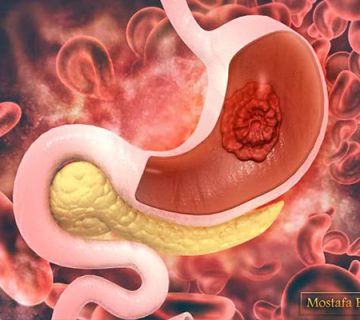

ساختار و عملکرد غده پروستات

پروستات غده ای در دستگاه تناسلی مردان است. این غده در لگن زیر مثانه و جلوی راست روده قرار دارد. پروستات در ساخت و ذخیره ی مایع منی نقش دارد. اندازه ی متوسط پروستات مشابه گردو است و اگر این غده بیش از مقدار طبیعی رشد کند و سرطانی شود دفع ادرار را کند می کند چون قسمتی از پیشابراه از غده پروستات می گذرد.